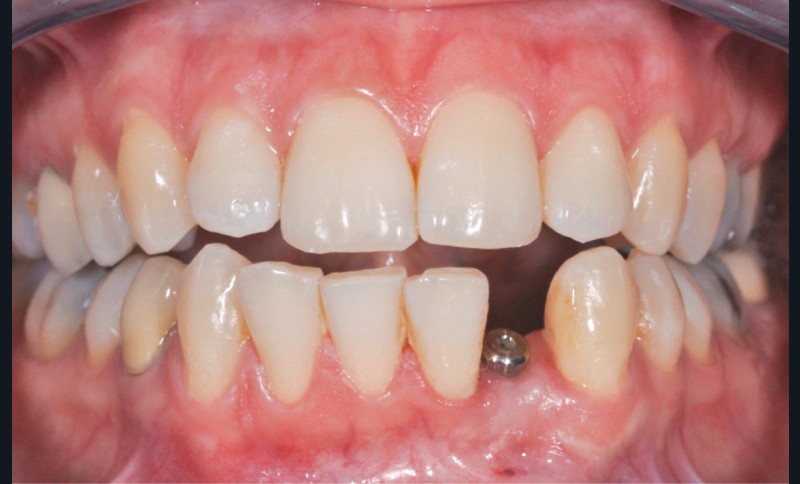

La prothèse implantaire plurale

Si les axes implantaires sont compatibles entre eux et esthétiquement, la solution vissée est préférable. Il est en effet plus compliqué d’éliminer les résidus de ciment lorsque le nombre de piliers augmente. Le fil dentaire ne peut être utilisé et le temps de travail reste identique à un seul pilier, ce qui s’avère parfois un peu court (fig. 8).

La plupart du temps, les deux sont possibles ; cependant, il existe des critères de choix pour orienter l’équipe thérapeutique.

Ainsi, une dent présentant une très petite face occlusale ou palatine/linguale peut indiquer une prothèse scellée pour des raisons mécaniques (voir fig. 9 page suivante).

Un axe trop divergent, même après système de correction d’axe, peut imposer la réalisation d’une coiffe scellée pour éviter un puits de vis sur un bord libre, par exemple (voir fig. 10, page suivante).

Lorsque les deux sont possibles, il faut plutôt privilégier la solution vissée.